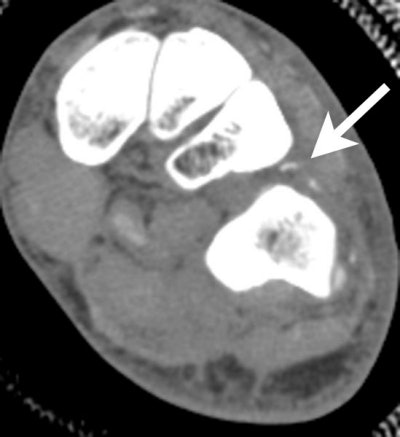

| Direct coronal CT image through the midfoot, demonstrating dislocation between the lateral cuneiform and the cuboid. Soft-tissue algorithms are routinely used in addition to bone algorithm in CT trauma evaluation to enable evaluation of tendons and ligaments. This soft-tissue image shows tiny avulsion fragments dorsally due to avulsion of the interosseous ligaments between the cuneiform and cuboid. |